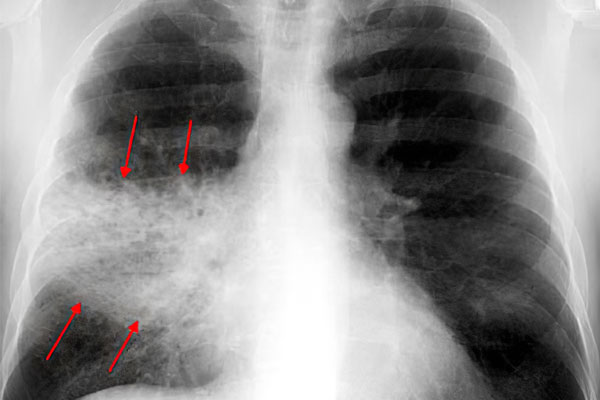

• Выполнение рентгенографии легких. Затемнения на снимках помогают выявить воспаленные участки.

Даже врачу без специальных анализов определить наличие пневмонии сложно. Основным методом диагностики этого заболевания служит рентгенография органов грудной клетки. Именно рентген помогает точно определить локализацию очага инфекции и её наличие.